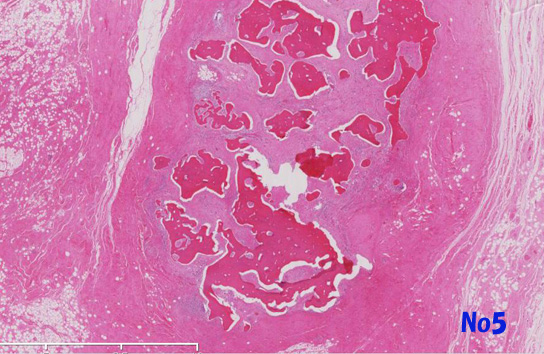

他の部分では異型細胞は, リンパ濾胞がよく発達した豊かな膠原線維性またはfibromyxoidな間質を伴って増殖しておりsclerosing and/or inflammaory variants of well differentiated liposarcomaの所見を呈する(Virtual Slide-No.3 and No.4) 。metaplastic ossificationが一部に認められた(Virtual Slide-No.5) 。

no5a.jpg